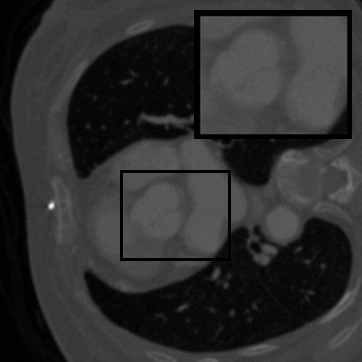

Figure 3: Qualitative completion results on TomoBank (lines 1 to 2) and LoDoPaB (lines 3 to 4) with random mask (ratio = 0.8) at 1024×\times1024 resolution. Odd columns and even columns show the sinograms and reconstructed images, respectively.

4.2.3 Completion Quality

Tab 2 summarizes accuracy results. At 2048×\times2048 resolution, HRSino achieves the best performance among all baselines while remaining memory-efficient, demonstrating its ability to extend high-quality completion to resolutions where other diffusion models fail. At 1024×\times1024, HRSino delivers accuracy comparable to its computation-intensive counterpart RePaint, showing that our optimizations do not compromise fidelity at moderate scales. Compared to DiffIR, MCG, TD-Paint, and HiDiffusion, HRSino consistently achieves higher SSIM and PSNR across mask ratios, with improvements up to +0.03 SSIM and +1.8 dB PSNR. Fig 3 visualizes sinogram completion and reconstructed images, where HRSino produces nearly indistinguishable results from RePaint. These findings confirm that HRSino fundamentally extends diffusion-based completion to 2048×\times2048 resolution in a more memory- and runtime-efficient manner.